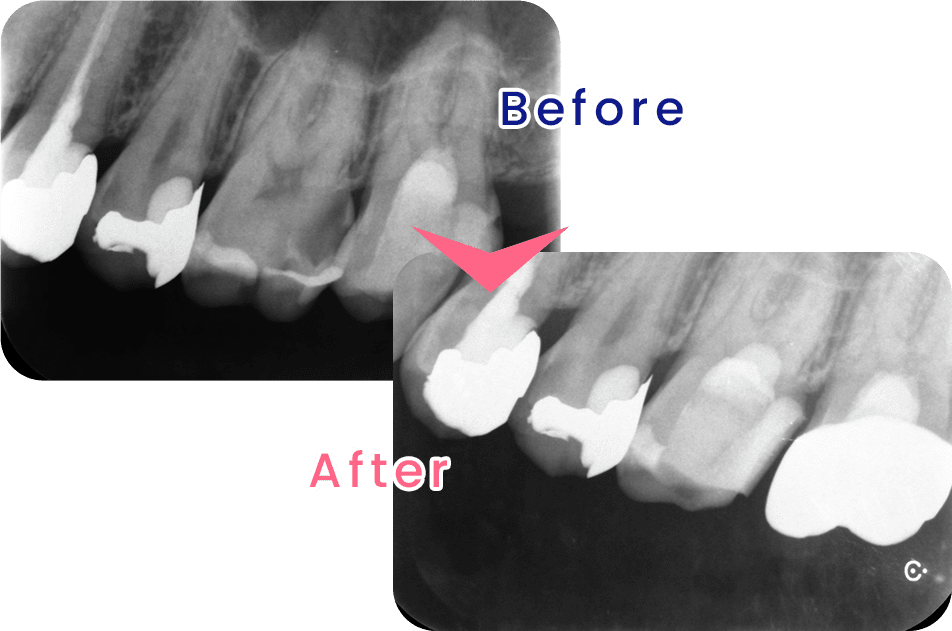

米国の歯内療法専門医が行う術式による治療です。先端設備と高度な治療を用いることで、従来の根幹治療では治療が難しかった症例でも、歯を残すことのできる確率を高めることが可能になります。

診療メニューには、虫歯治療、歯周病治療、インプラント治療、詰め物・被せ物、入れ歯治療、口腔外科、予防歯科、